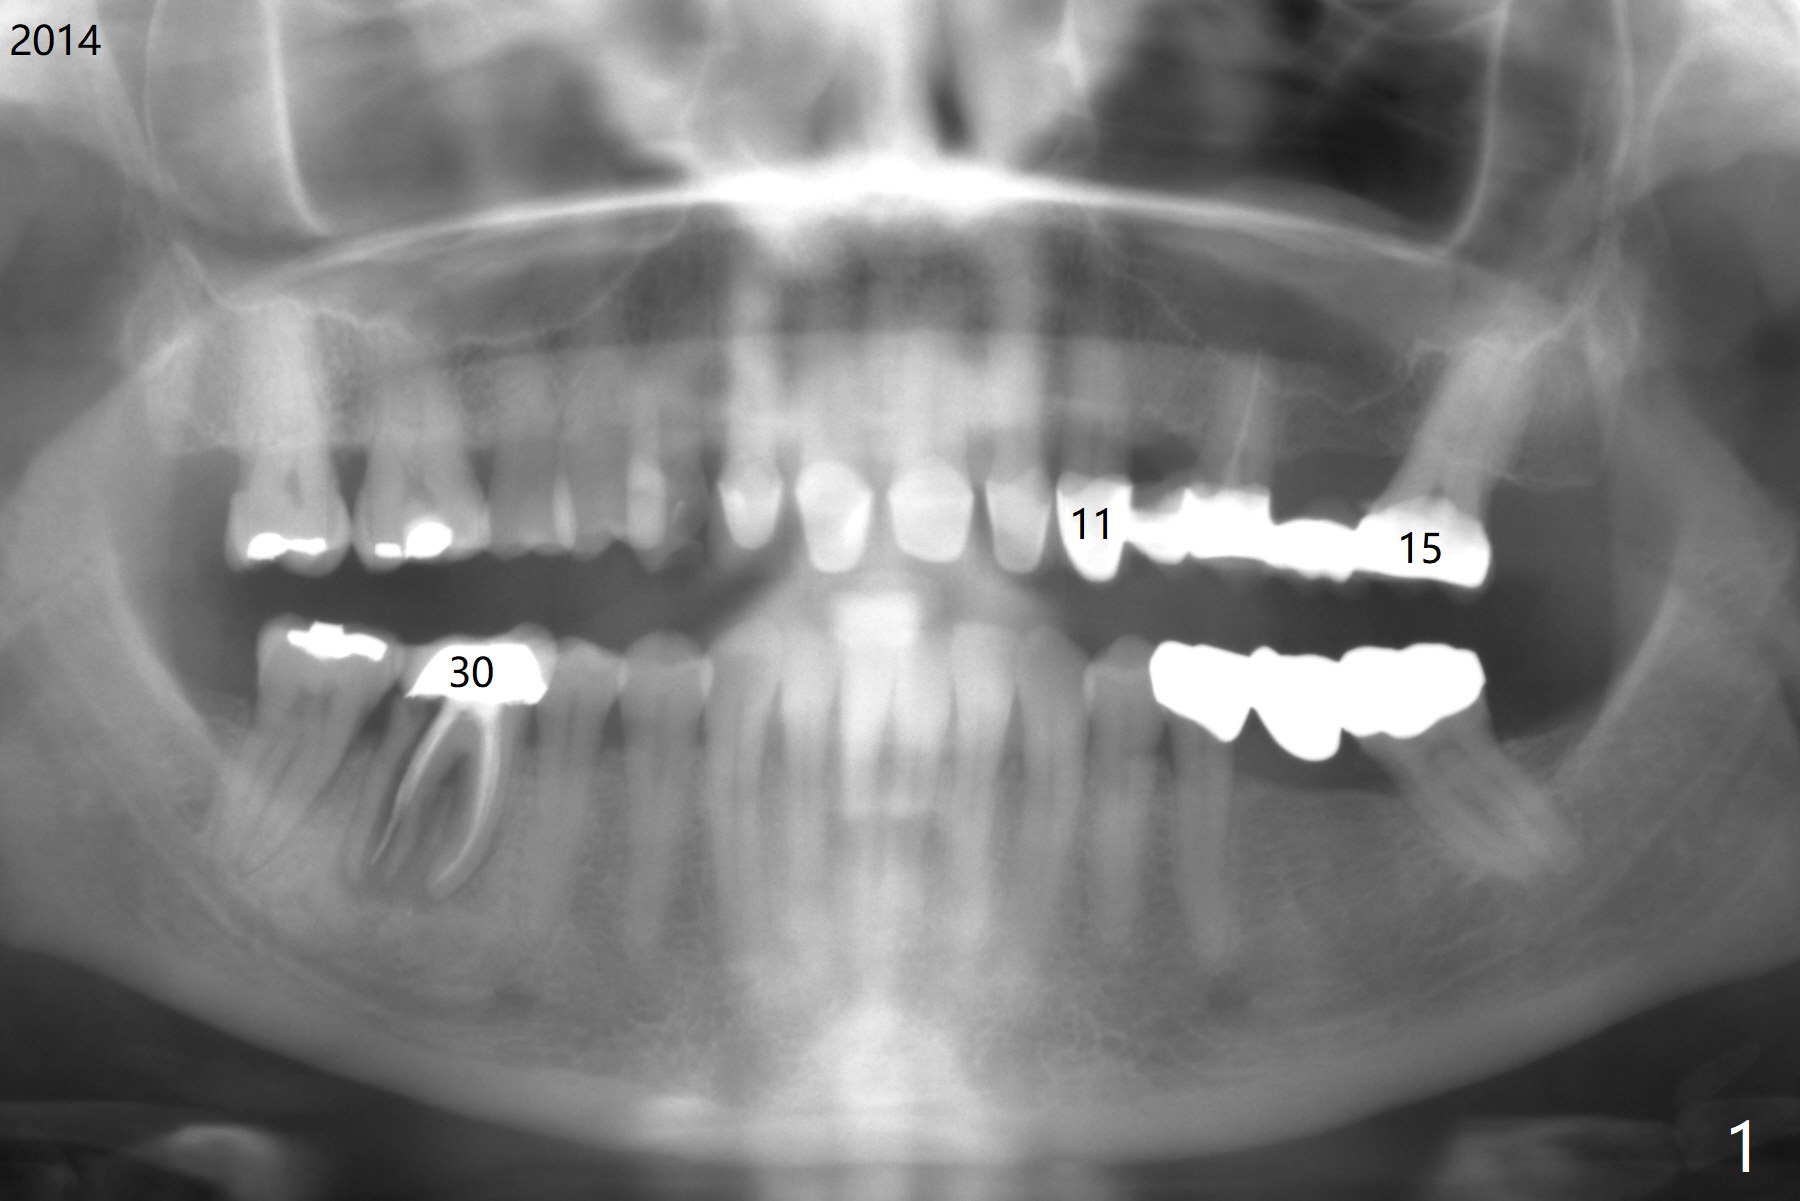

A 55-year-old woman is a bruxer (Fig.1). In 5 years the upper left FPD is fractured between #11 and 12 (Fig.2) and at #15 (Fig.3). Sectioning the FPD shows #15 non-salvageable (Fig.4). Implants will be placed at #12, 14 and 15. Sinus lift seems necessary at #14 (4 mm).